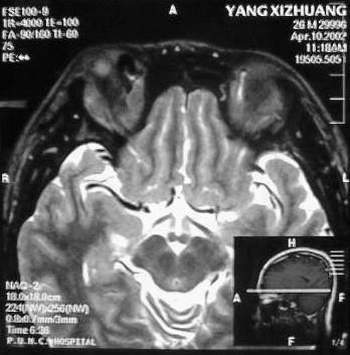

MRI及增强结果如下:

患者压颈及其它Valsava试验结果阴性。从MRI分析,在T1、T2、T+C检查该支血管均为明显流空现象,说明该血管血流速度很快,而从走行和分布看,眼上静脉可能性很大。也许也不能除外异常的眼动脉或异常血管。眶内主要可能的血管病变包括颈内动脉海绵窦瘘(高流窦)、AVM、眼眶静脉曲张、海绵状血管瘤、静脉性血管瘤、毛细血管瘤和眶内动脉瘤。。 1、颈内动脉海绵窦瘘:该患者临床有一部分支持该诊断。但从影像分析,海绵窦未见明显扩张;眼外肌未见明显充血扩张的长T1、长T2信号;颈内动脉海绵窦瘘常可见继发到血栓,可见到短T1、长T2的血栓信号。 2、眼眶静脉曲张:该疾患一般常见于小儿。该患大多数会出现Valsava试验阳性,间歇性突眼。不符合该患。影像学检查,于曲张静脉内常可见血栓和静脉石。所以不符合该患。 3、AVM:患者目前的影像学资料尚不全面,但可符合该诊断。临床上改病常见于30岁左右年轻人,单侧发病,于本患较符合。问题在于临床没有明确的血管杂音,似乎难以解释。 4、该患影像学与海绵状血管瘤差别很大,所以可基本排除此诊断。 5、静脉性血管瘤和毛细血管瘤:MRI中等T1、长T2信号,较易与本病鉴别。 6、眶内动脉瘤:我觉得患者并不能排除本病,但同样,由于波动性阴性,似乎也难以解释。 纵上所述:本人觉得,患者AVM可能性较大,同时不能除外眶内动脉瘤。 关于进一步检查,我觉得DSA价格过于昂贵。是否可先进行彩色多普勒检查,首先可以明确是静脉系统还是动静脉瘘抑或是动脉瘤。第二步,可进行MRA检查,可以清楚地显示海绵窦地相关关系,并可借此诊断或排除颈内动脉海绵窦瘘。如还需第三部检查,可进行MRV检查,对静脉系统进一步评价。三种检查总共的费用2000多圆,但给予我们的信息量已经很丰富了。 敬请各位医师提出自己的见解。 谢谢!

根据MRI显示眼上静脉扩张可能性很大。眼上静脉扩张有几种原因:1.颈内动脉海绵窦瘘,2.眶尖肿瘤,3.甲亢,4.炎性假瘤.病人球结膜充血示静脉回流障碍,动脉瘤可能性小.根据病史,我认为排除1,2.则考虑3,4.查T3,T4.激素作诊断性治疗.